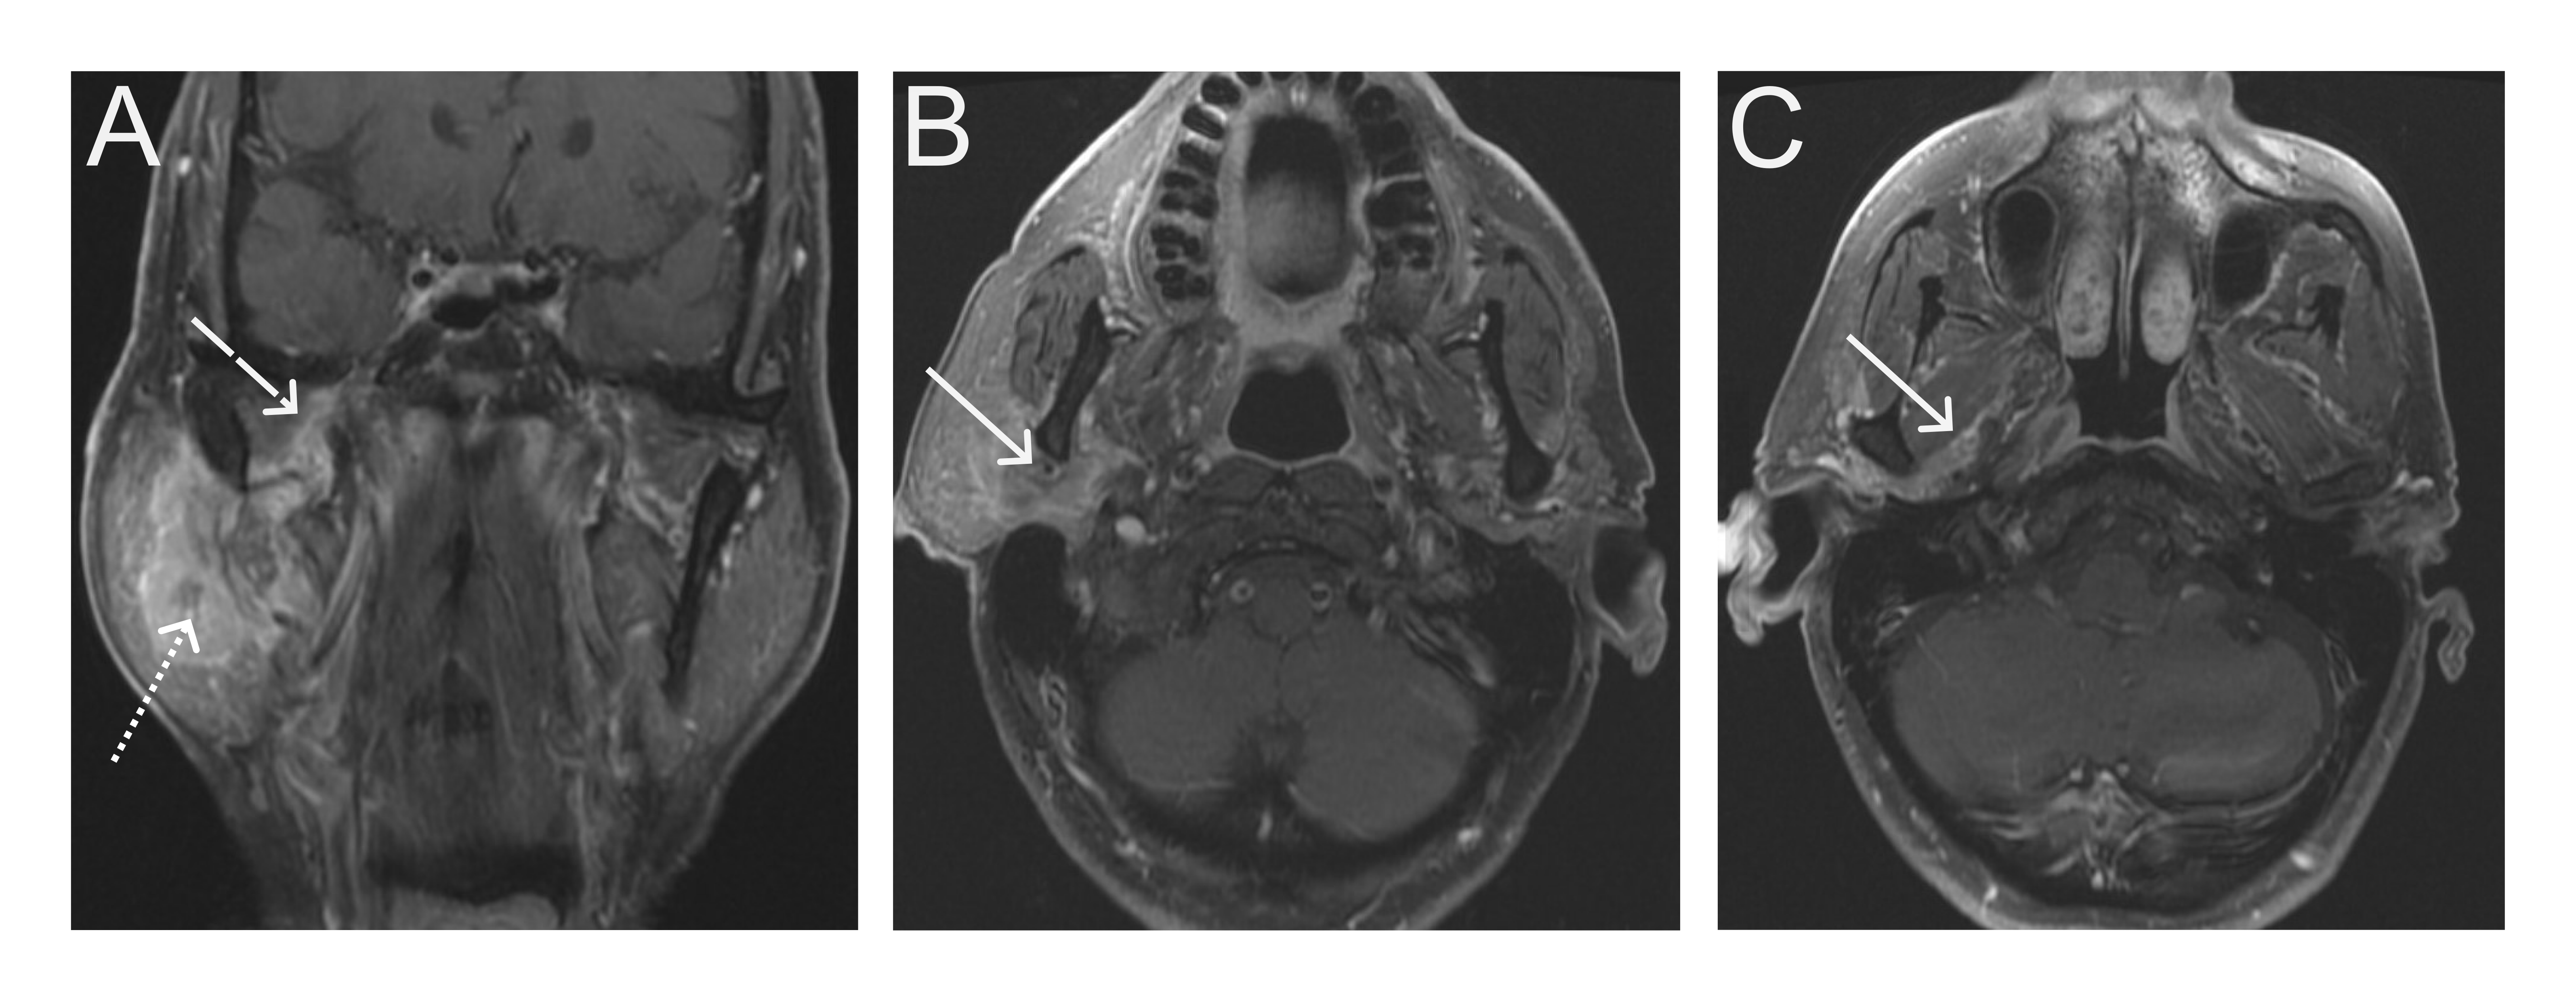

• EMG was performed a month after symptom onset (cf. figure 1)

Evolution

Capture d e cran  le 2025 06 04 a  10.52.59

Figure 1. Electrodiagnostic study performed at 1 month since symptom onset.

Sensory nerve conductions show a decreased amplitude of the median nerve response (5.7 μV) and a distal latency increased by 3.5 in favor of demyelinating damage.

Motor nerve conductions show prolongation of median, ulnar, tibial and fibular nerve latencies.